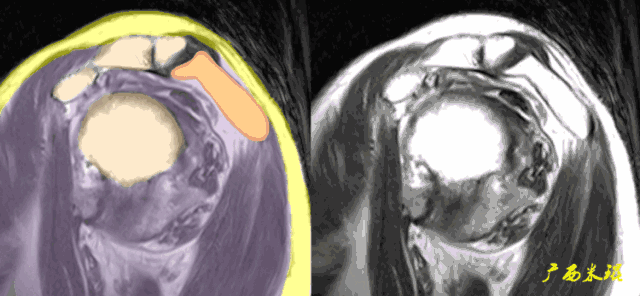

i、盂肱关节关系异常,在斜冠状面上看到肱骨头的上移,肩峰与肱骨头间隙狭窄是肩袖巨大撕裂的表现。

盂肱关节关系异常在轴位片上也可能看到,一般是由于肩胛下肌或冈下肌和小圆肌的撕裂后力量不平衡所造成。